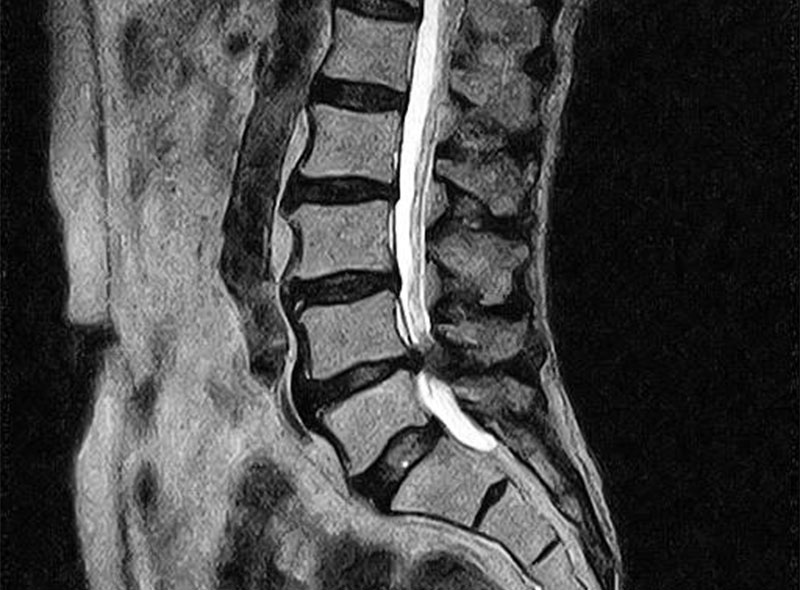

MRIを使った検査・診療

レントゲンでは評価することが出来ない靭帯や骨の状態を詳しく評価することができます。

靭帯損傷や腰椎圧迫骨折や腫瘍の正確な診断が可能です。

当院のMRIはオープン型ですので、狭い空間が苦手な方も少ないストレスで検査を受けることが出来ます。

MRI検査画像

腰椎(脊柱管狭窄症)